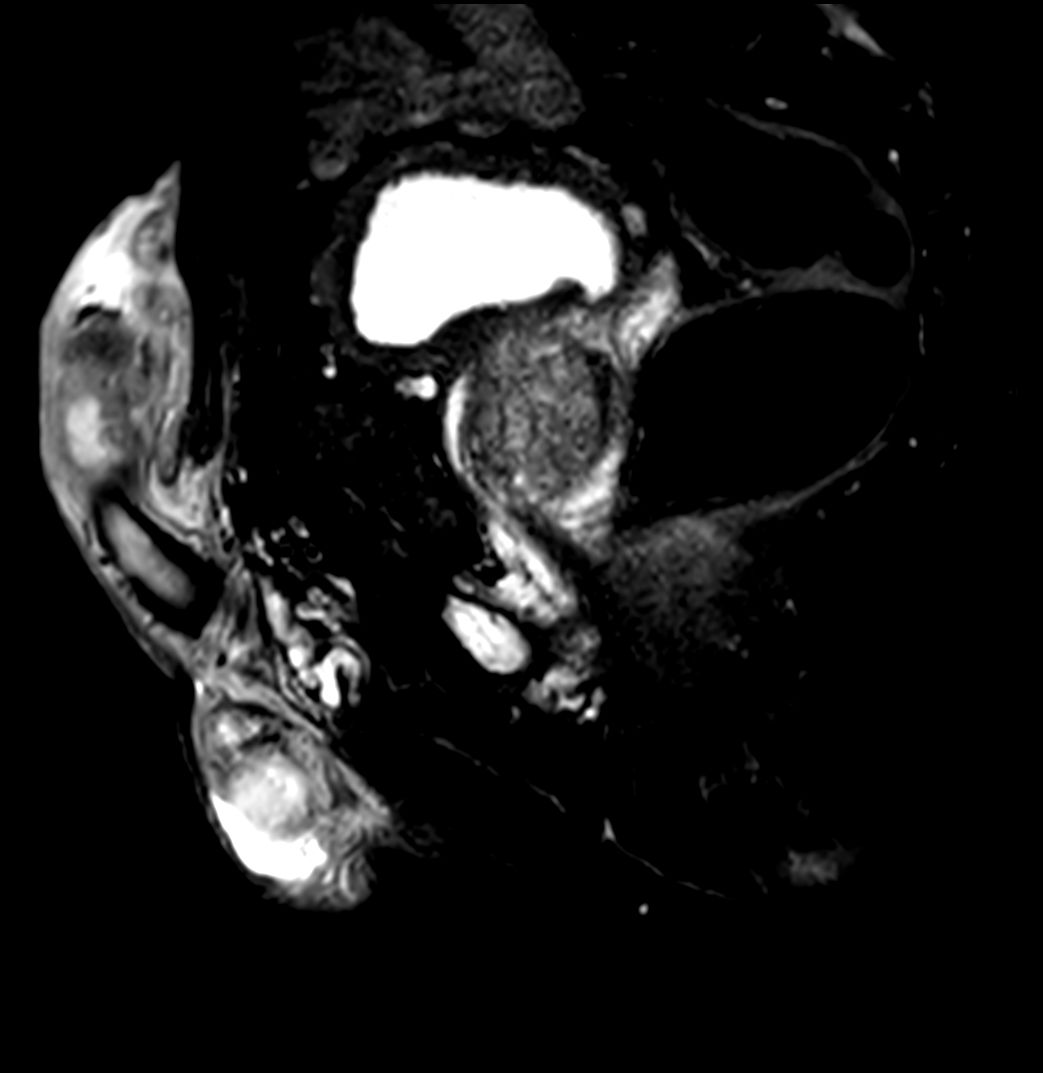

Patient with a penile carcinoma. ExamCard includes Compressed SENSE to shorten exam time, diffusion to achieve high contrast between background and lesions, and MultiVane XD for motion-free imaging in short scan time.

T1w TSE +gado Compressed SENSE

T1w TSE FatSat +gado Compressed SENSE